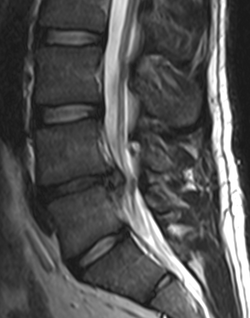

Slikovna je dijagnostika opravdana kada su prisutni upozoravajući znakovi, neurološki simptomi koji ne prolaze, te kontinuirana bol ili bol u pogoršanju.[8] Konkretno, rana upotreba slikovne dijagnostike (MRI ili CT) preporuča se kod sumnje na tumor, infekciju ili cauda equina sindrom.[8] MRI ima veću osjetljivost od CT-a za identifikaciju bolesti diska; obje tehnologije su jednako korisne u dijagnostici spinalne stenoze.[8] Samo nekoliko fizikalnih dijagnostičkih testova je korisno.[8] Test podizanja pružene noge je gotovo uvijek pozitivan u onih s hernijom diska.[8] Lumbalna provokativna diskografija može biti korisna u identifikaciji specifičnog uzroka boli u onih s jakom kroničnom boli u donjem dijelu leđa.[23] Slično tome, terapijski postupci poput blokade živca mogu se koristiti u određivanju specifičnog izvora boli.[8] Neki dokazi podupiru primjenu injekcija u fasetne zglobove, transforminalnih epiduralnih injekcija, te sakroilijačnih injekcija kao dijagnostičkih testova.[8] Većina drugih fizikalnih testova, poput procjene skolioze, slabosti ili trošenja mišića, poremećaja refleksa, od male su koristi.[8]